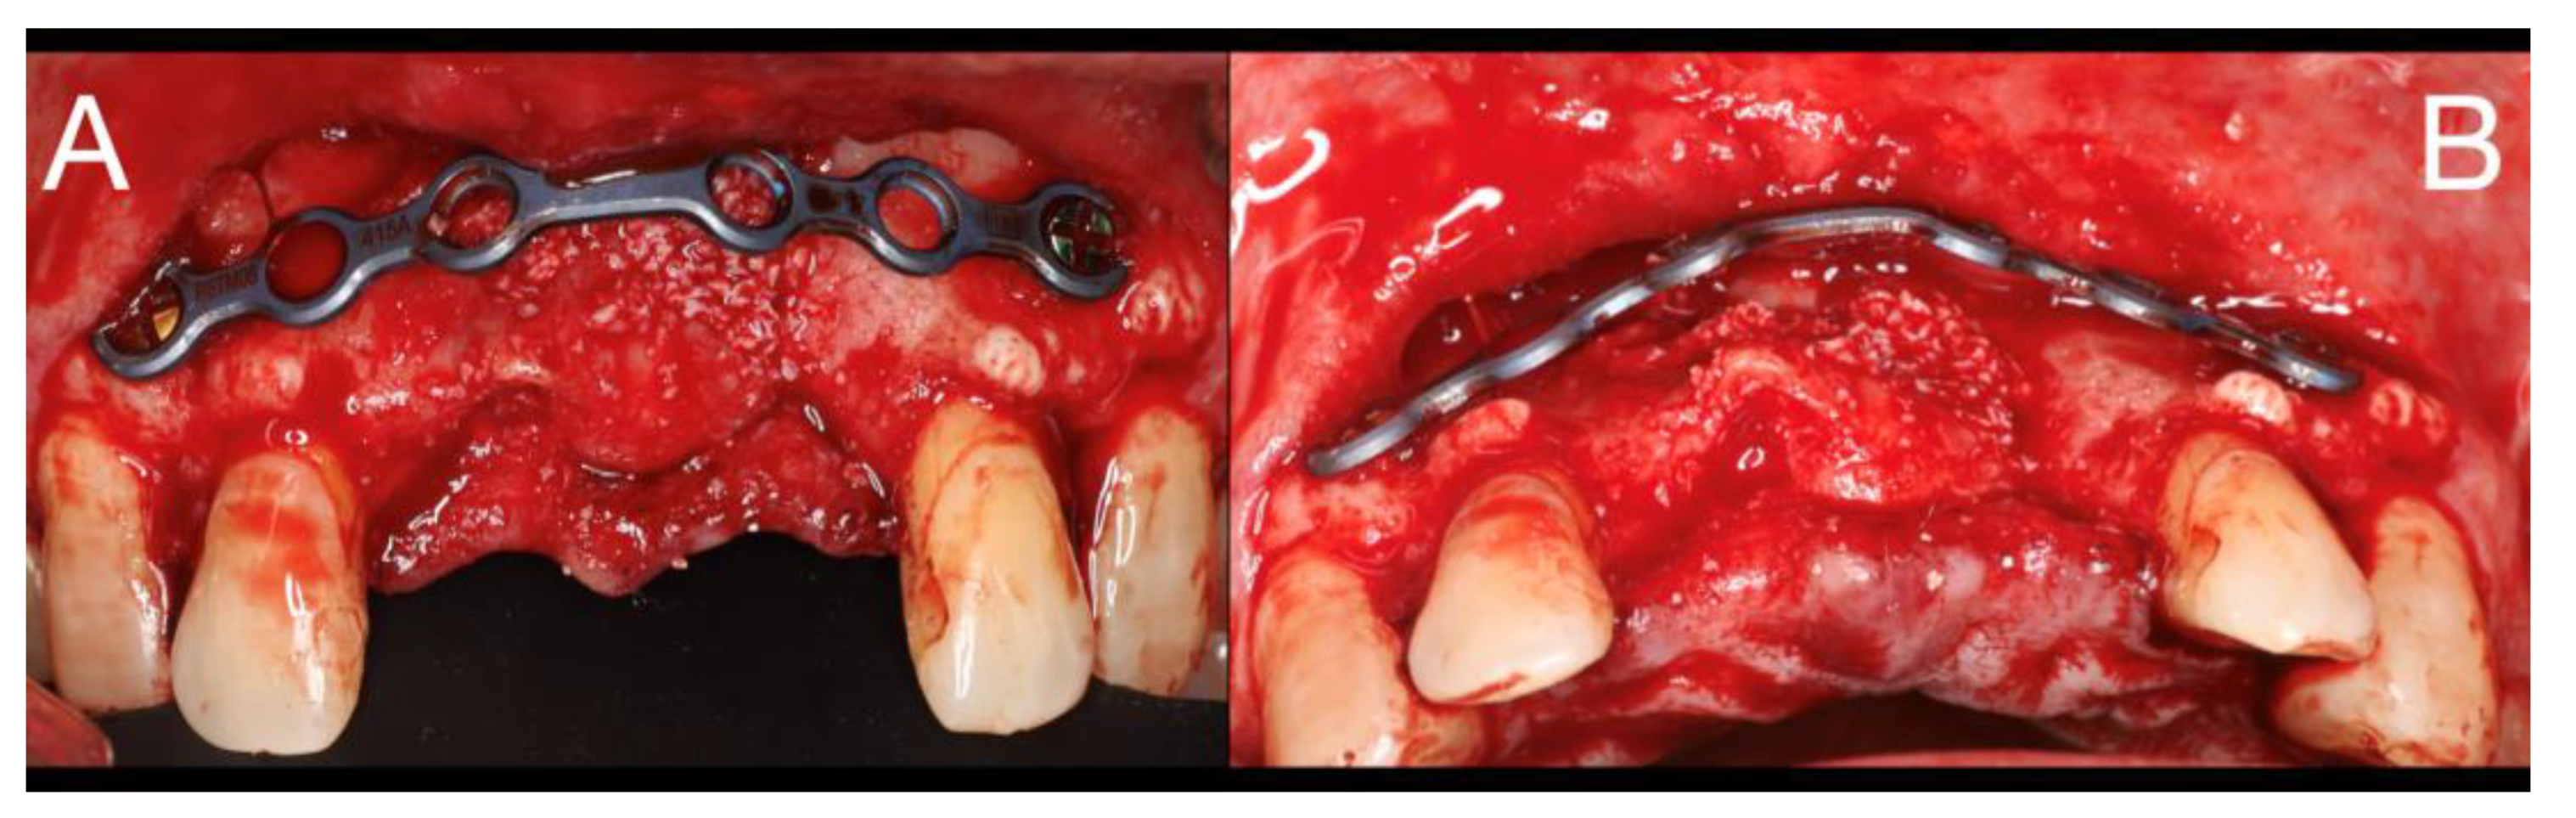

A titanium straight plate with 0.8 mm of thickness (Global D, Brignais®, France) was molded to give the shape of the alveolar ridge and fixed with two screws (Figure 6) and the released periosteous incisions was performed with a 15 blade.

Figure 6. The titanium plate mold to give the shape of the alveolar ridge and fixed with two screws; xenograft placed at the cyst cavity – A -frontal view; B - occlusal view.

Preprints 77316 g006

Figure 7. The gap between the bone and the plate filled with particulate xenograft – A - occlusal view; B - frontal view; the xenograft covered with a collagen membrane fixed with pins – A - occlusal view; B - frontal view.

Preprints 77316 g007